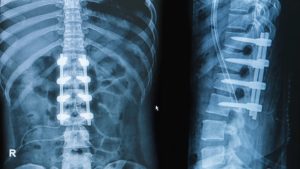

Для стабилизации деформированных позвоночных сегментов проводится операция, во время которой на позвоночный столб крепятся титановые пластины или другие металлоконструкции.

- Транспедикулярная стабилизация. С помощью специальной ножки (педикулы) в смежные позвоночные тела вставляется корригирующая металлическая конструкция в виде винтов, крепко соединенных между собой штангами. Подобная техника чаще всего применяется при смещении или переломе позвонков.

Техника стабилизации поврежденных позвонков подбирается специалистом в индивидуальном порядке, учитывая множество факторов: тип повреждения, возраст и состояние здоровья пациента, наличие противопоказаний. Для операции могут применяться различные металлоконструкции: винты, пластины, стержни, скобы.